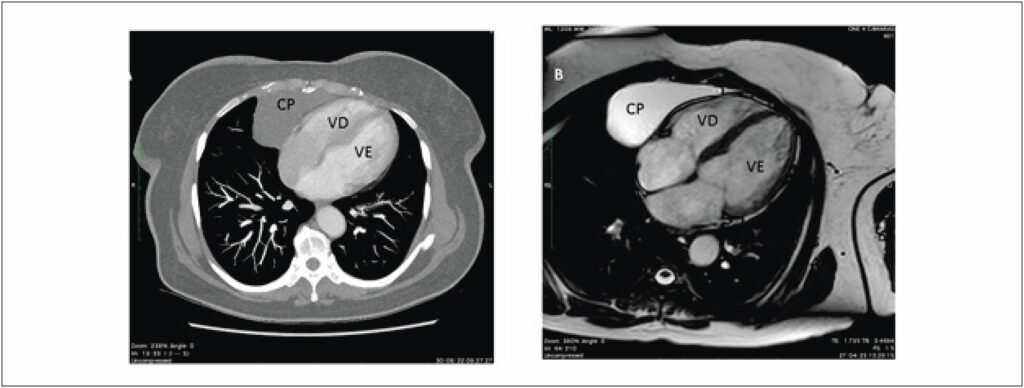

Paciente do sexo feminino, 59 anos, portadora de hipertensão arterial sistêmica, diabetes mellitus e dislipidemia, foi encaminhada a um serviço terciário para investigação de tosse irritativa, não produtiva, surgida dois meses antes. Negou sintomas de refluxo ou empachamento pós-prandial, bem como congestão nasal ou sinais de rinite alérgica. Negou tabagismo, etilismo e contato com indivíduos com tuberculose e não relatou eventos pneumônicos prévios.